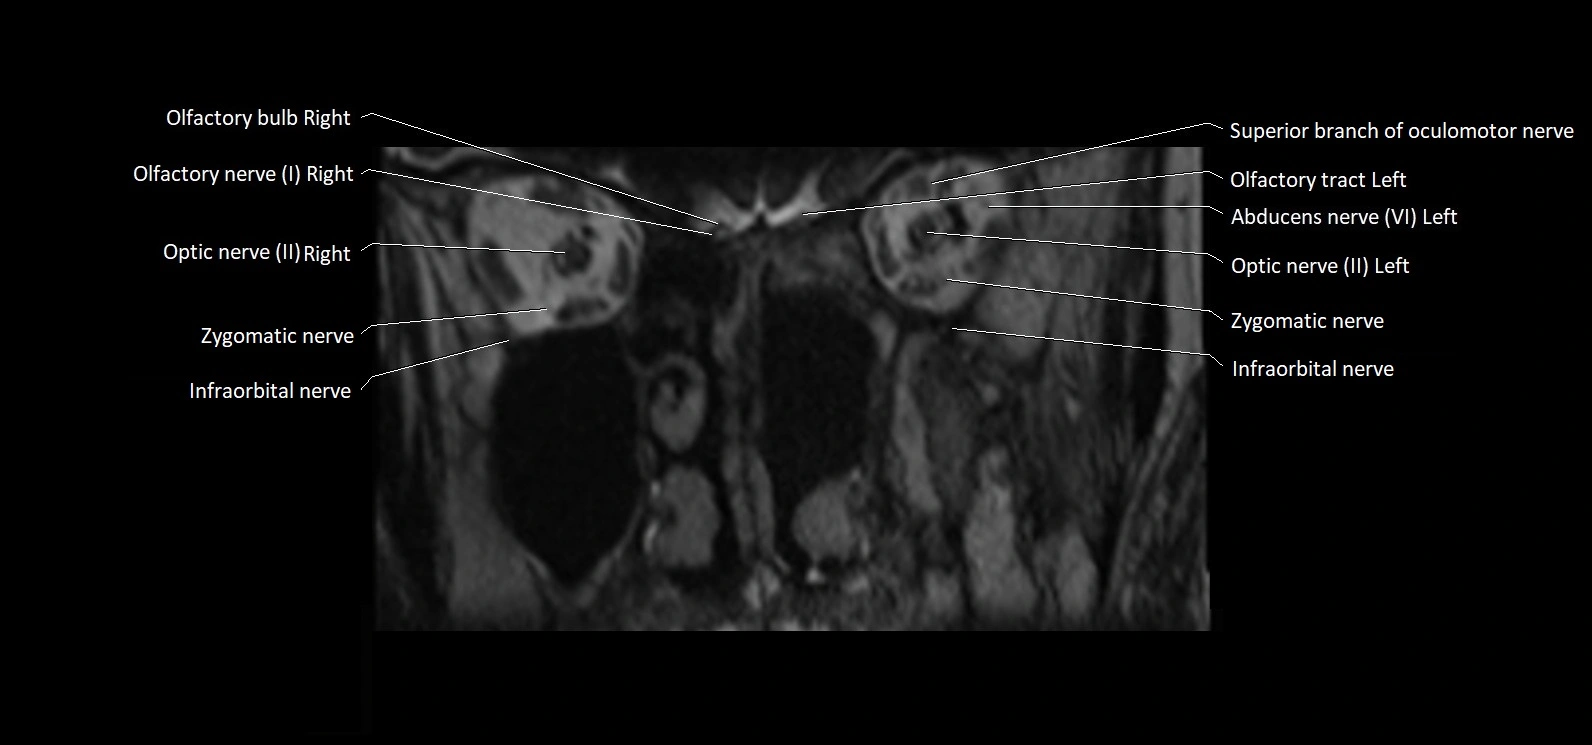

MRI Appearance

• The abducens nerve is a small, thin, linear structure

• Best visualized on high-resolution T2-weighted 3D MRI sequences (e.g., FIESTA or CISS)

• Seen as a hypointense (dark) line running from the brainstem at the pontomedullary junction, traversing the prepontine cistern, and entering Dorello’s canal under the petrosphenoidal ligament, then into the cavernous sinus, and finally the orbit

• May be challenging to visualize in standard MRI due to its small size

• Pathology may be inferred by absence, displacement, or enhancement of the nerve